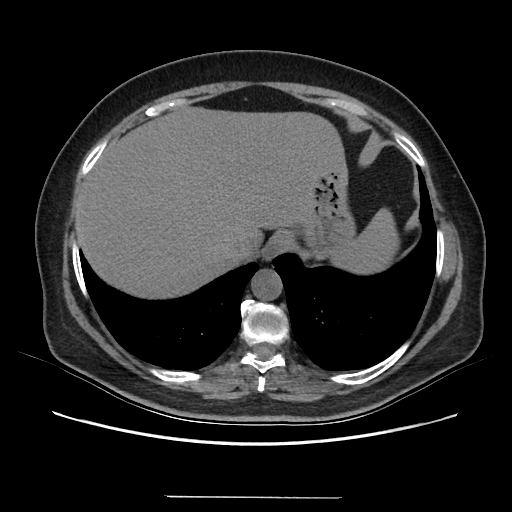

Image Grid

4Γ—3 grid: Rows show different image types (Original NATIVE, Reconstructed NATIVE, Original VENOUS, Generated VENOUS), Columns show windowing techniques (No Window, Lung Window, Mediastinum Window)

Original NATIVE CT scan (input)

No window - Raw intensity values

Original VENOUS CT scan

Generated VENOUS CT scan (A→B translation)